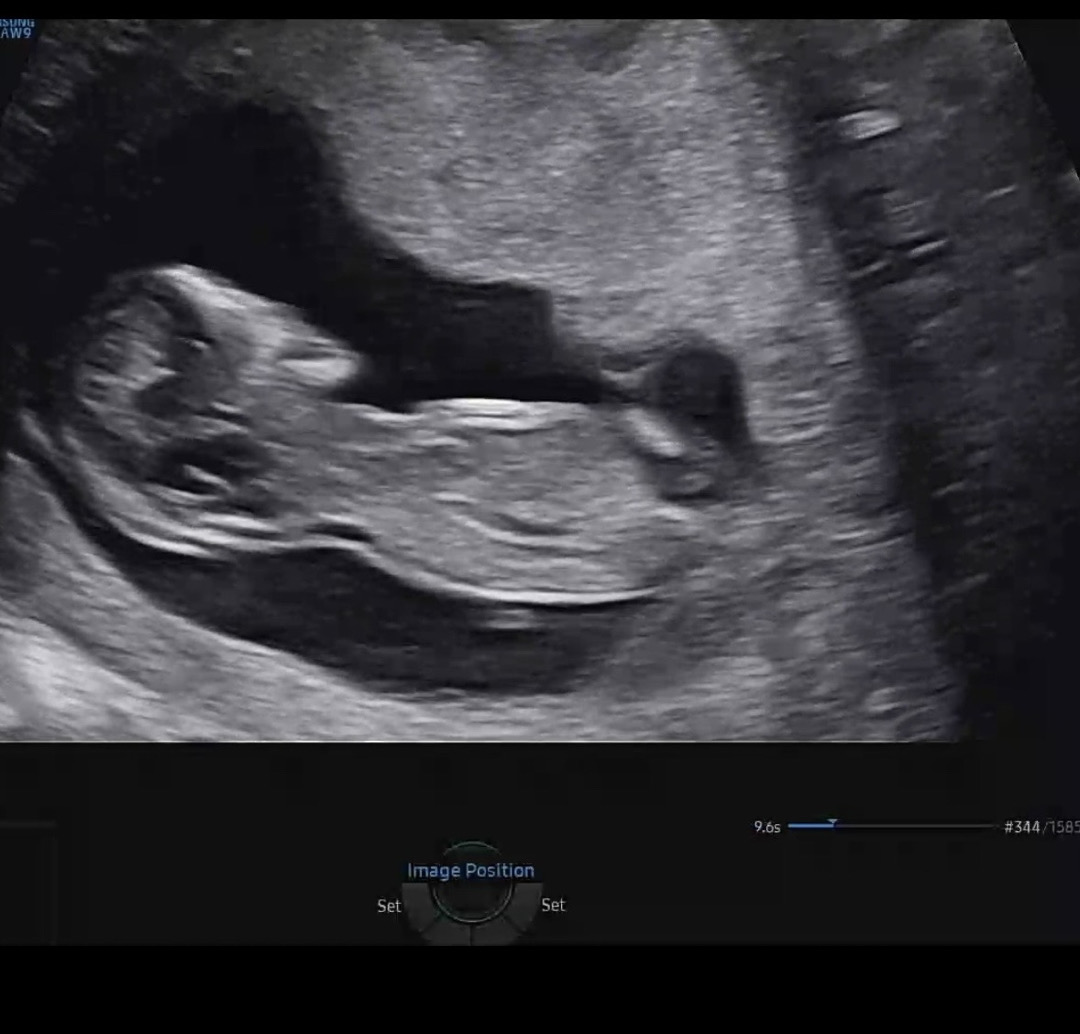

12주 각도법 봐주세요

각도법 부탁드립니다~